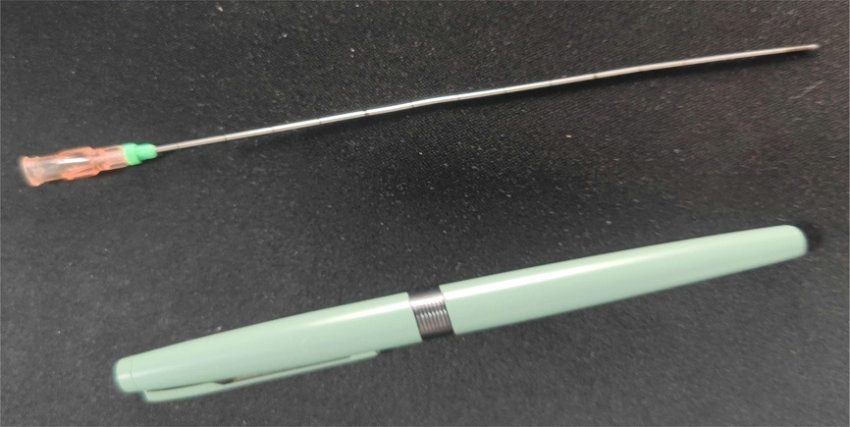

介入穿刺针

放射性粒子植入属于组织间植入近距离治疗范畴,是放射治疗的方法之一,主要通过影像引导技术(CT、彩超、磁共振)通过介入穿刺针,像子弹一样将密封的放射源直接打入肿瘤病灶内,通过放射性核素持续释放射线对肿瘤细胞进行杀伤的一种治疗手段。放射性碘-125粒子能以27-35kev能量放射出γ射线,半衰期为60.2d。γ射线有效辐射半径10-15mm内肿瘤细胞的DNA,干扰肿瘤细胞DNA合成,诱导细胞凋亡,杀灭肿瘤细胞,小血管,小神经等,达到缩小肿块,缓解疼痛的目的。放射性粒子在治疗实体肿瘤具有精度高、创伤小和疗效肯定等优势,近年来3D打印模版技术的发展进一步提高了精度、安全性,缩短了手术时间。